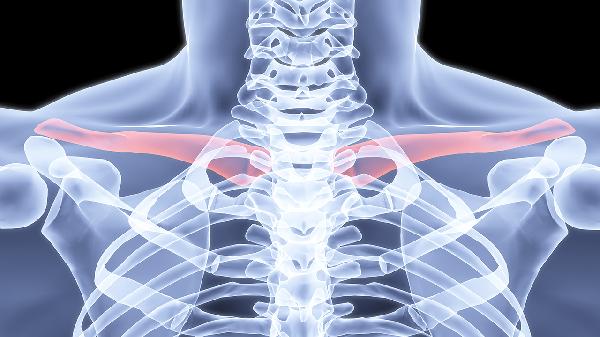

锁骨骨折通常采用八字绷带或锁骨带固定,严重移位需手术钢板内固定。钙片无法替代物理固定,但可为骨痂形成提供原料。固定期间需定期复查X线观察对位情况。